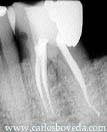

La evaluación radiográfica muestra lo extenso de la restauración, el compromiso pulpar y el estado del ligamento periapical.

Imagen radiográfica orto-radial final.